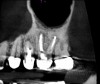

Surveying pulpal anatomy before initiating treatment is another area in which CBCT can benefit a trained operator. Understanding the internal anatomy of the root canal system can help in treatment planning a nonsurgical case, as well as a microsurgical case, to avoid procedural mishaps. CBCT can also facilitate the conservation of tooth and root structure.For instance, knowing whether a maxillary molar has a second mesiobuccal (MB) canal can help the practitioner avoid troughing or removing precious dentin when there is no MB2 canal. In addition, more accurately locating the MB2 canal when it is visible on CBCT also assists in conserving tooth structure. The same holds true for a possible lingual canal or additional canal(s) in a mandibular incisor (Figure 9) or bicuspid.

Fig 9. 3D CBCT image of mandibular incisors with two canals.

Figure 9